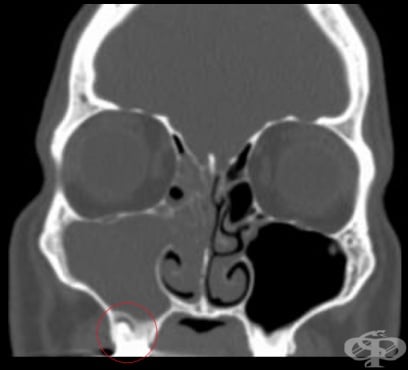

Синузит, причинен от зъбни проблеми

Синузитът, причинен от зъбни проблеми (одонтогенен максиларен синузит) е възпалителен процес от зъбен произход, локализиран в горночелюстната кухина. Той обхваща предимно синусната лигавица и по-рядко костните структури. Възпалението се дължи на непосредствената близост на корените на горните зъби...

Синузит Възпалени синуси Синузит Симптоми при синузит Синузит Синузит Риноскопия Рентгенография максиларен синузит Компютърна томография етмоидакен синузит ЯМР синузит Одонтогенен синузит Лечение на синузит

СинузитВъзпалени синусиСинузитСимптоми при синузитСинузитСинузитРиноскопияРентгенография максиларен синузитКомпютърна томография етмоидакен синузитЯМР синузитОдонтогенен синузитЛечение на синузитЛечение на синузит